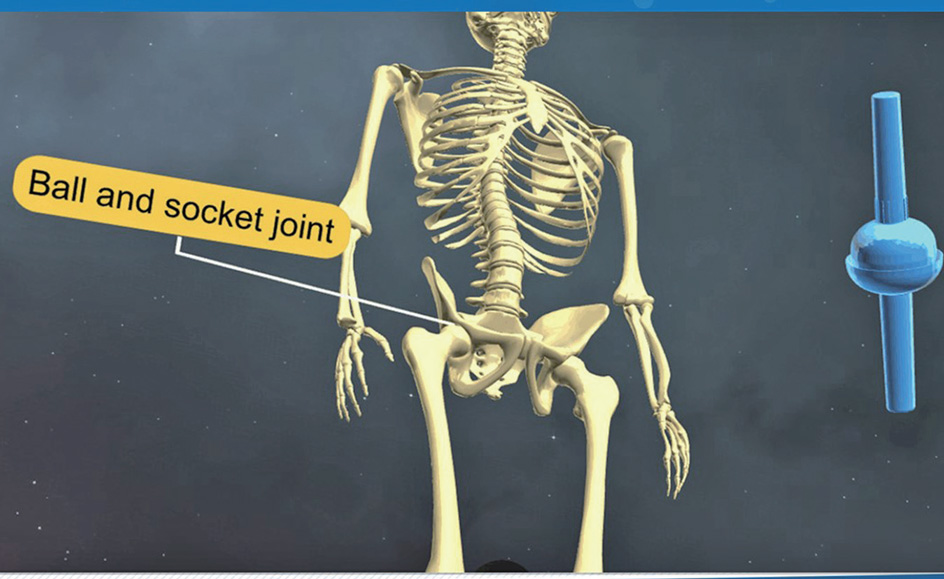

- 가동관절⑥ 절구관절

자동차 엔진에 엔진오일이 없다면 빡빡해져서 피스톤 운동이 제대로 안 되겠죠. 마찬가지로 항상 움직여야 하는 가동성 관절면은 섬유피막으로 쌓여 있고 이 내부의 막에서 매끄러운 윤활액을 분비해 부드럽게 움직일 수 있어서 이 모든 가동관절을 윤활관절潤滑關節(Synovial joint)이라고도 부릅니다.